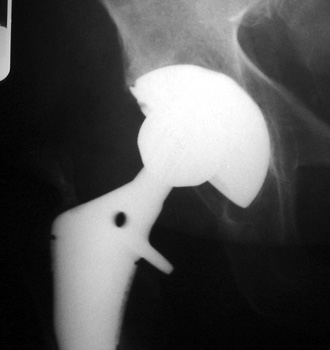

Severe polyethylene liner wear with associated osteolysis of ischium and proximal femur